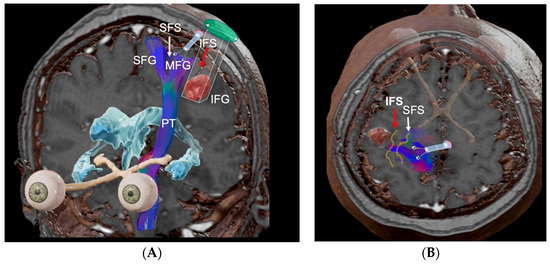

2.5. Eight Step Strategy for PTA Design